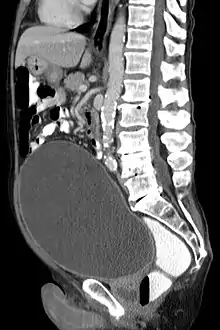

Urinary retention with greatly enlarged bladder as seen by CT scan.

As seen on axial CT